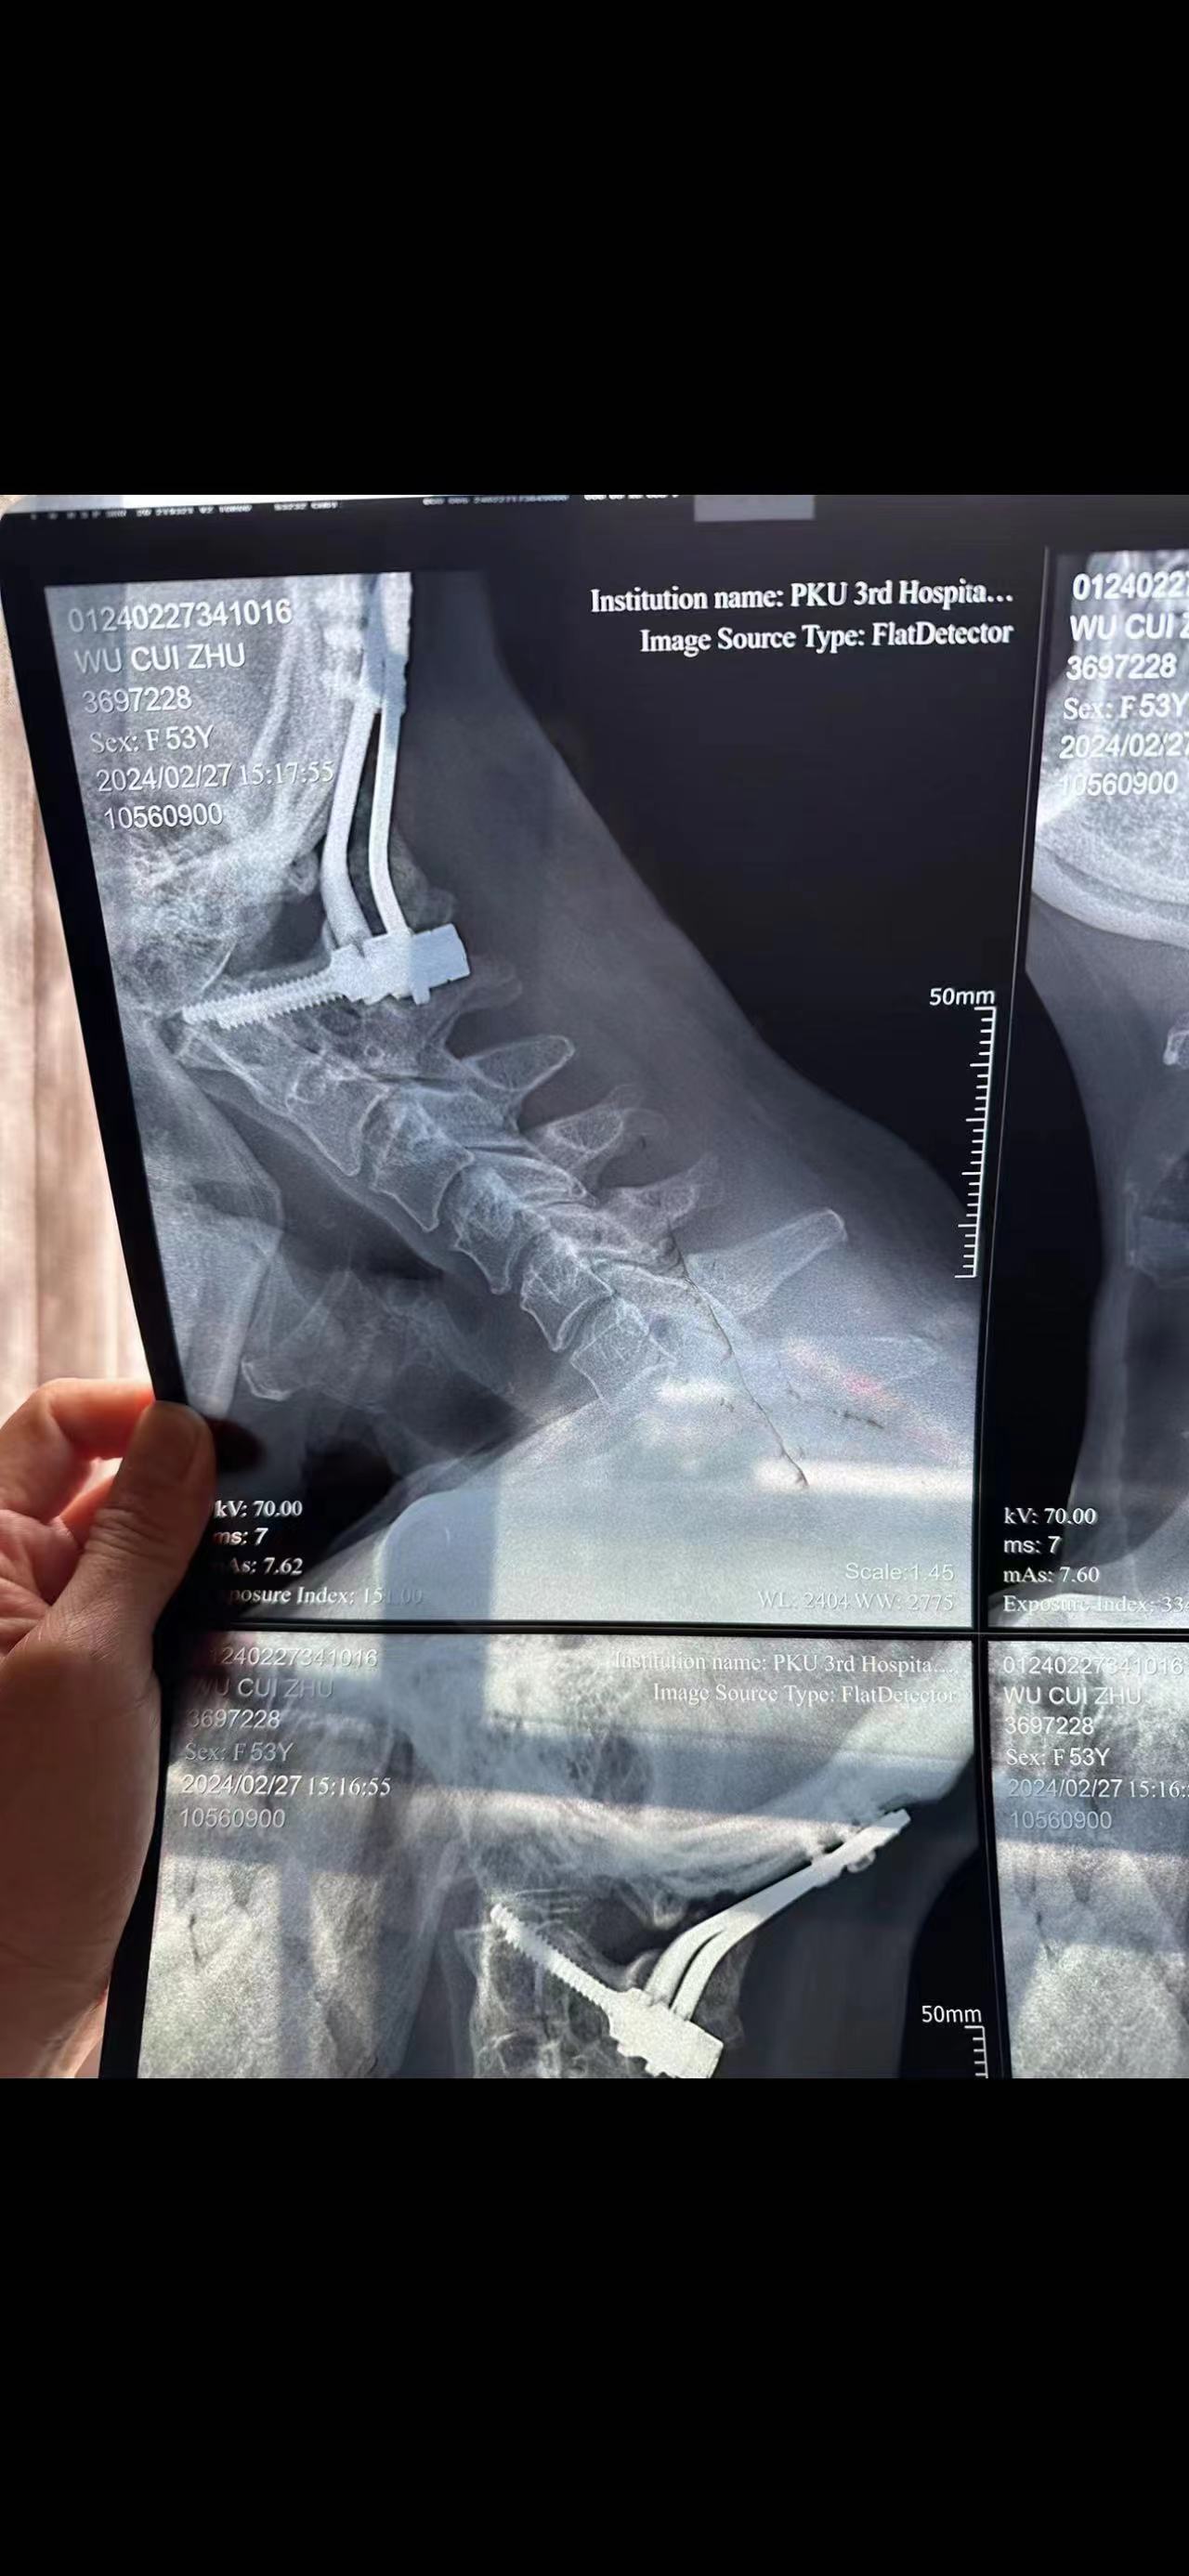

• 日期:2023.09

• 医院:北三医院

• 主刀:王超

• 术后影像:

• 2024.02.27,复查,对位良好,偶尔会肩甲骨酸,坐下就不酸。